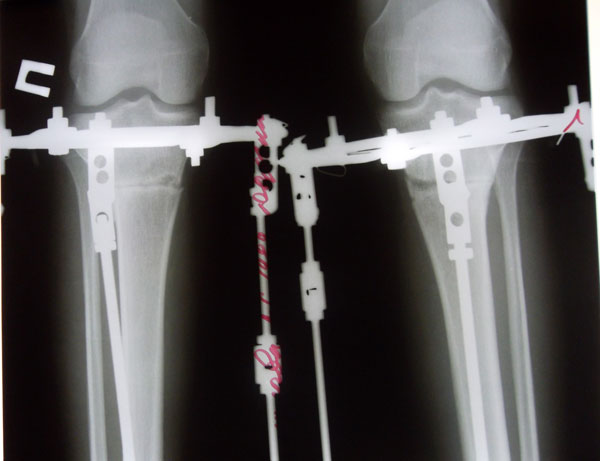

Рентген на 69-ый день с момента ОП. Сегодня была в клинике, проведывала своих подружек, не сдержалась и сделала себе рентгеновский снимок с позволения Николая Николаевича, хотя планировали через неделю. Рентген отличный, можно думать о снятии, но потом придётся поберечься и ограничивать себя в нагрузке ещё недели 2-3. Значит будут страдать посещения занятий в универе, а зачем? Сейчас я хожу совершенно свободно, как здоровый человек и моя походка не привлекает взглядов посторонних глаз. В универе бегаю и летаю по лестничным пролётам, никаких скидок ни в чём мне никто не делает, а мне это даже приятно. Хотя желание освободиться от аппаратов конечно же есть. Чтобы не страдал учебный процесс, с моим доктором со снятием аппаратов решили подождать ещё 2-3 недели.

Сегодня была в клинике, сделала контрольный рентген обеих голеней в 2-х проекциях.

Николай Николаевич посмотрел мои рентгеновские снимки и сказал что можно снимать аппараты. Сращение хорошее.

Мне распустили аппараты для воспитания регенерата(костной мозоли). Через 7-10 дней пойду на снятия аппаратов.